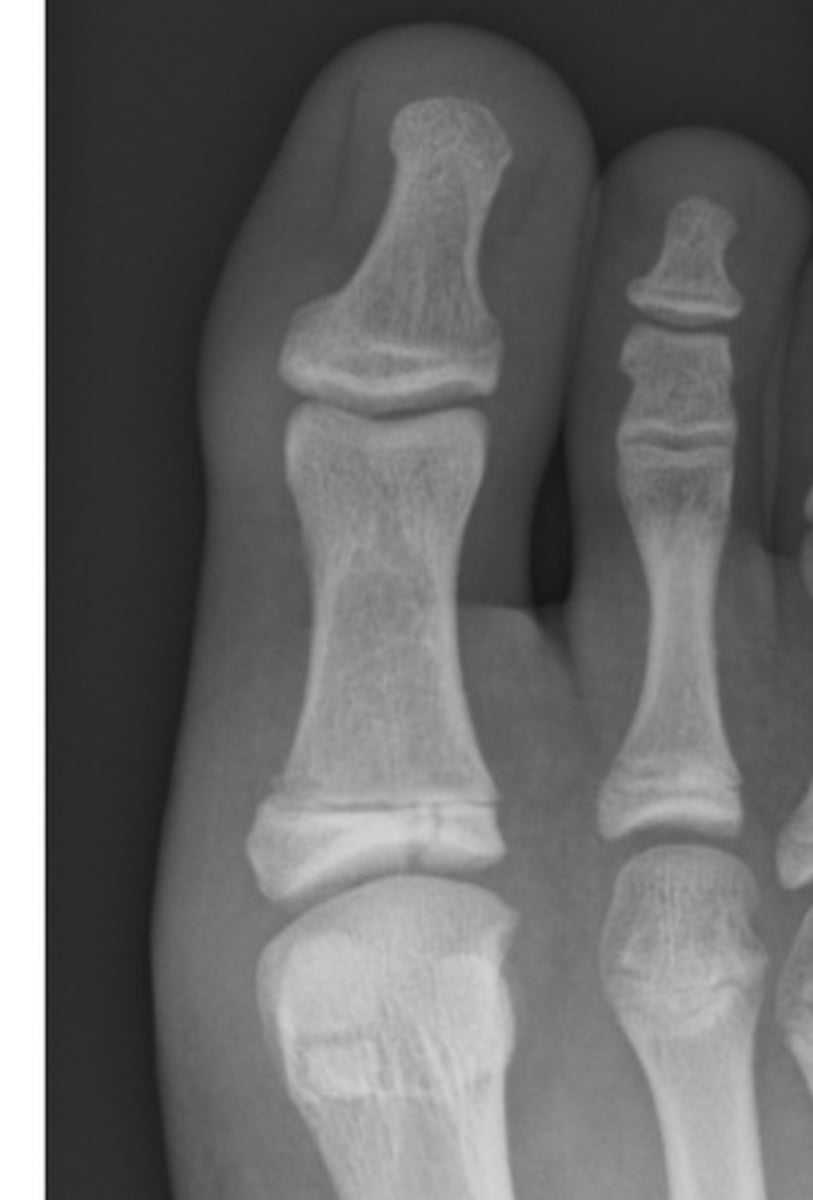

There is a transverse to slightly oblique fracture through the waist of the scaphoid, with no significant displacement or carpal malalignment. Additionally, there is an oblique intra-articular fracture at the base of the first metacarpal, extending into the carpometacarpal joint. The distal metacarpal fragment is displaced proximally and dorsally, consistent with a Bennett's fracture, with associated subluxation at the CMC joint.

dislocation of the proximal phalanx of the big toe at the MTPJ (metatarsophalangeal joint)